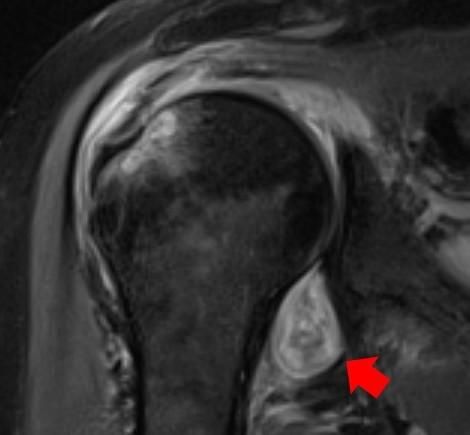

Radiologists can use X-rays and CT scans to identify features left by non-ferromagnetic ballistic fragments, opening the door to MRI imaging for some patients.